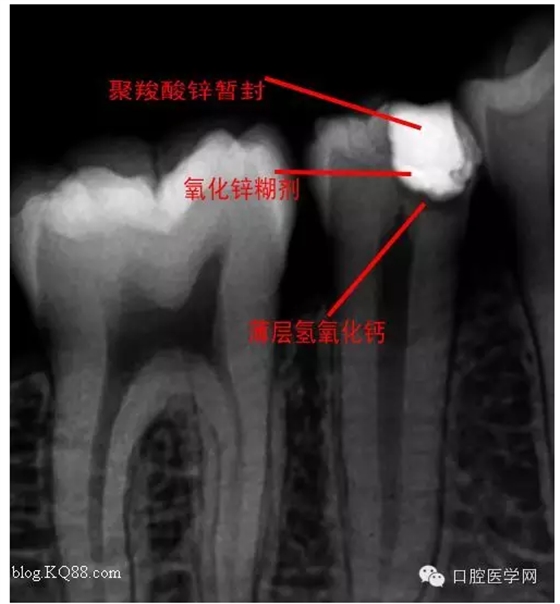

去腐,備洞。發(fā)現(xiàn)已經(jīng)露髓。根據(jù)年輕恒牙保存活髓治療原則。選擇直接蓋髓術(shù)?;颊呤俏业闹种辣4婊钏璧闹匾?,所以只是做了簡單的溝通。如果其他病人遇到這種情況術(shù)前溝通很重要。首先灌輸保髓的重要性,告知術(shù)后反應(yīng),以避免不必要的麻煩

術(shù)后第二天問小伙:什么反應(yīng)?答:輕微脹痛,無冷熱痛,無咬合痛。我驚愕因為回答的夠?qū)I(yè)。不愧是金牌助手。呵呵,如果病人這樣回答您會???在啰唆幾句:操作中無菌是關(guān)鍵。從露髓的一刻起就不應(yīng)與唾液接觸。去腐后生理鹽水沖洗窩洞,但不要加壓或生理鹽水棉球輕輕擦拭窩洞。柔風(fēng)吹干